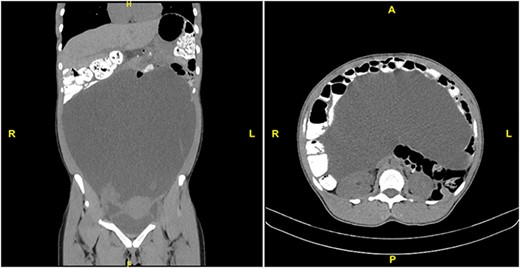

A 31-year-old healthcare worker with no medical history presented to her gynecologist complaining of 2 months of abdominal bloating and increasing abdominal girth. She denied nausea, vomiting, abdominal pain, changes in bowel habits, fevers or chills. She was taking iron supplements only. She denied family history of gynecologic or gastrointestinal cancer, recent or distant travel, and had always had negative PPD tests. Review of systems was unrevealing. Physical exam was notable for a tense, nontender, distended abdomen. CBC showed WBC count 2.4 × 103 without other abnormalities (Table 1). Blood chemistries, liver function tests, amylase and lipase were within normal range. CA 19–9 was slightly elevated at 40.3 (N < 35) and other tumor markers including AFP, CA125, CEA, CA 27–29 and albumin were within the normal range. Ultrasound and noncontrast CT of the abdomen and pelvis revealed massive ascites, as well as displacement of abdominal organs superiorly and inferiorly to the ascitic fluid (Fig. 1). All organs appeared normal, but evaluation was limited by the mass effect of the ascites. Aside from an endometrial polyp, there was no evidence of abdominal masses or nodules.

CT scan with PO and IV contrast demonstrating massive ascites and displacement of abdominal viscera. Left: coronal section. Right: transverse section at L1.